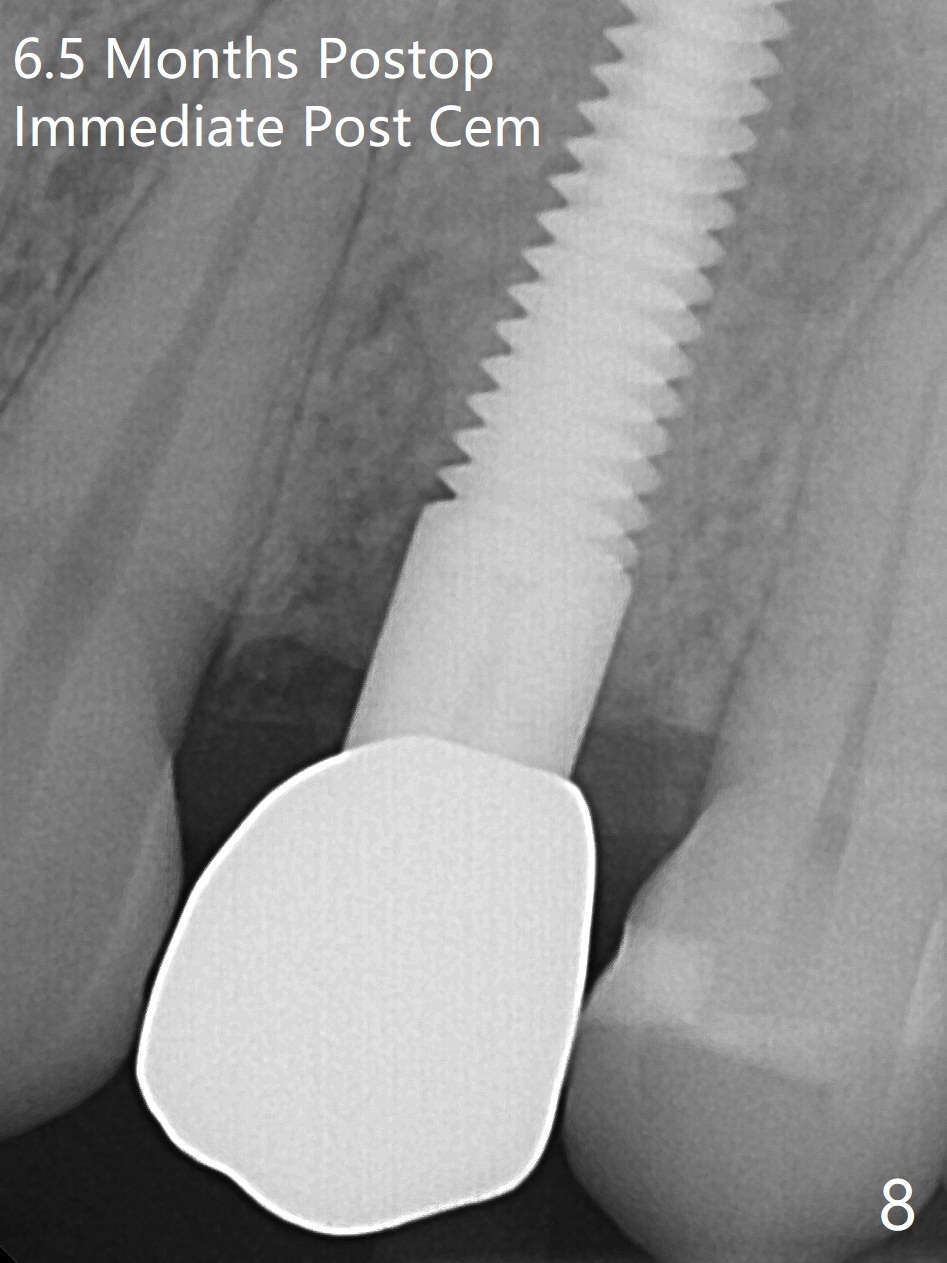

Since there is no buccal plate atrophy at 4, or 8, socket shield is not attempted at #31. Extraction turns out to be difficult because of tooth fracture. The buccal and palatal flaps have to be elevated minimally for tooth sectioning and purchase point formation. More surprising, a 4.5 mm implant appears to be too wide for the space; a 4x17 mm implant achieves insertion torque >60 Ncm (Fig.1,2). In fact Vanilla graft is placed before and after implantation. The advantage of bone graft before implant is that the graft is able to be placed as apical as possible to repair the apical defect if it is present. The disadvantage is hemorrhage. After placement of a 3.5x5 mm abutment, an immediate provisional is fabricated (Fig.3 P), which seems to be able to hold the separated buccal papillae in place. The latter heal around the immediate provisional 9 days postop (Fig.4). Because of the seal, the bone graft remains in place 1 month postop (Fig.5). There is no bone loss 5.5 months postop (Fig.6,7) or 6.5 months postop (immediately post cementation, Fig.8).